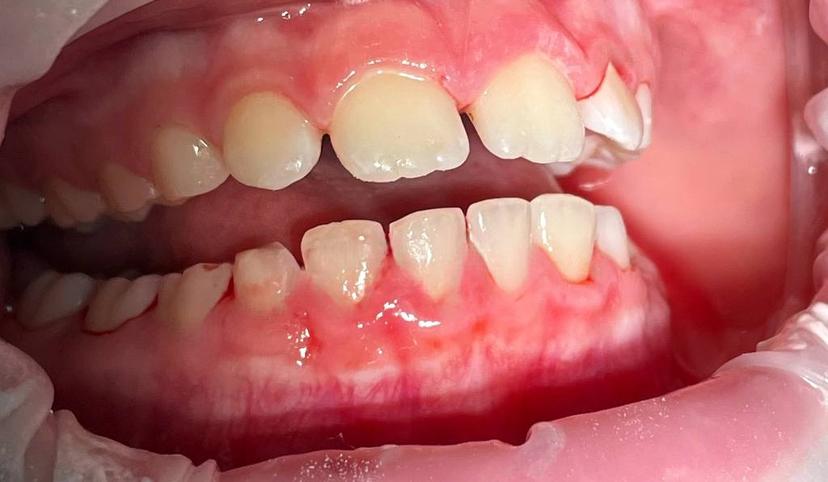

Пигментированный зубной налёт "Присли" у пациента 11 лет.

Профессиональная гигиена проводилась при помощи аппарата Air Flow, позволяющего удалить зубной налёт. Завершающим этапом было полирование зубов, которое позволяет сократить дальнейшее образование налёта.